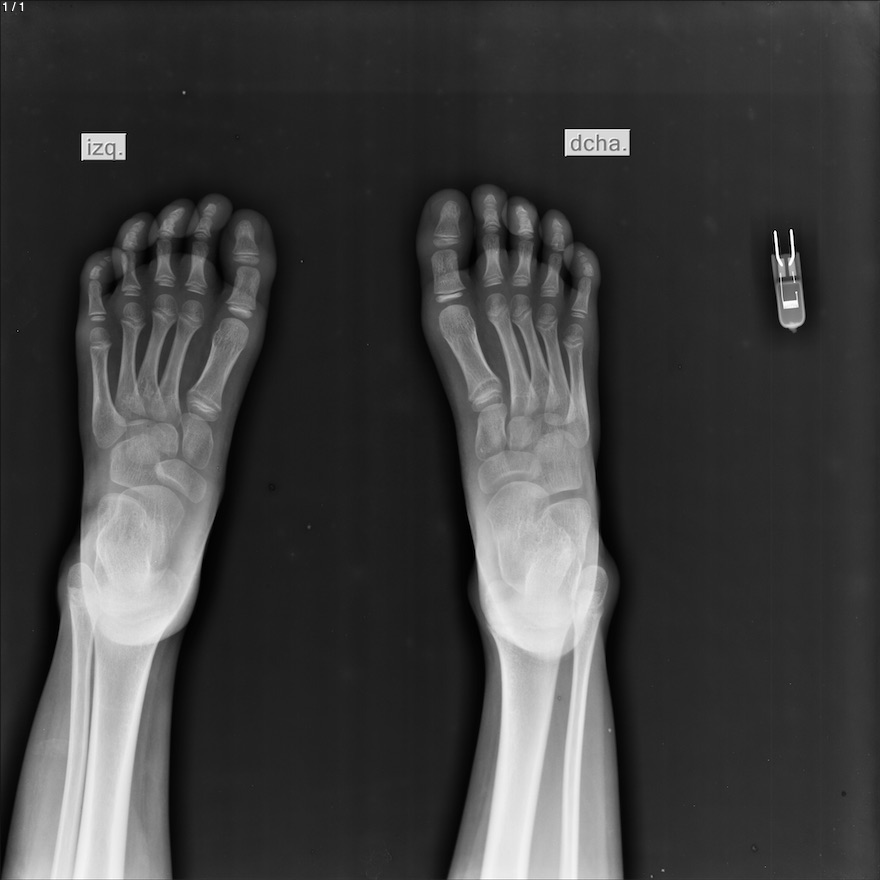

Danna Sophia Vazquez Enriquez - Unnamed